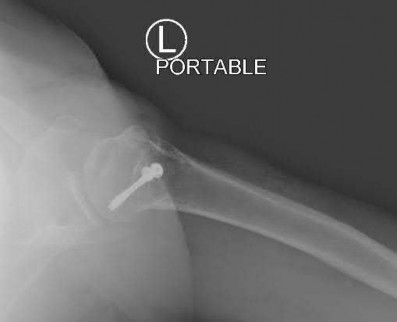

Question 12:

A 55-year-old patient presents with a slowly enlarging, painful mass in the proximal humerus. Biopsy reveals a hyaline cartilage matrix with cellular atypia, confirming a diagnosis of central conventional chondrosarcoma. Which of the following genetic mutations is most frequently identified in this specific tumor?

Correct Answer: IDH1 / IDH2

Explanation:

Mutations in the isocitrate dehydrogenase genes, IDH1 and IDH2, are found in up to 50-60% of central conventional chondrosarcomas and enchondromas. EXT1 and EXT2 mutations are characteristic of multiple hereditary exostoses (osteochondromas). GNAS mutations are seen in fibrous dysplasia. TP53 and RB1 mutations are hallmark aberrations in osteosarcoma.